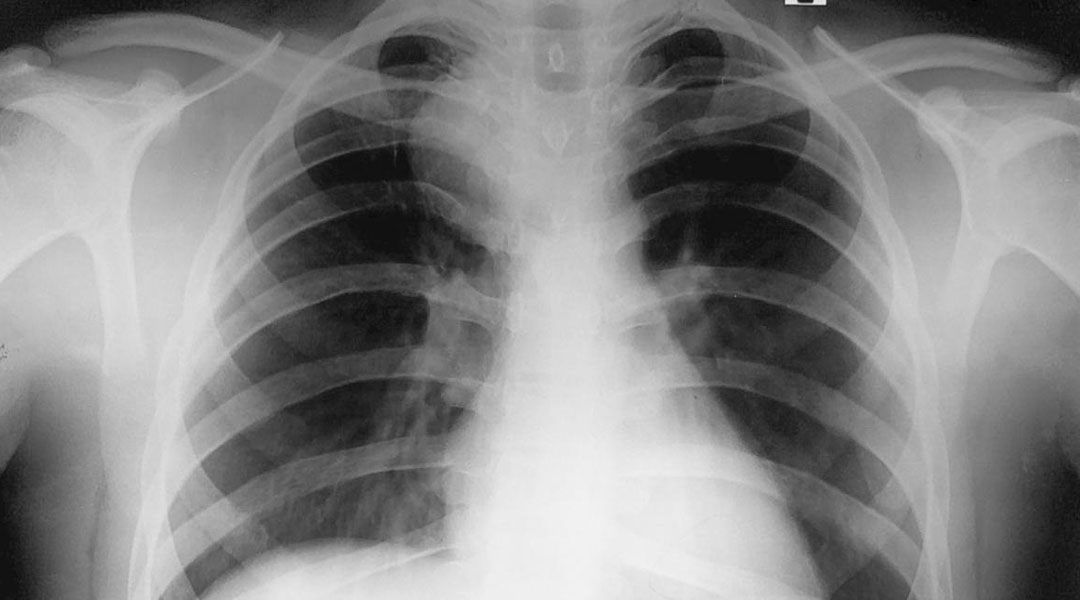

Bronchogenic cysts are often discovered incidentally during imaging tests such as:

• Chest X-ray